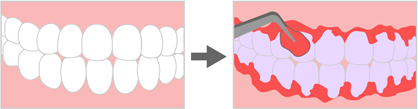

1.染出し

歯垢染色液を使用して歯の汚れている箇所を染出し、歯垢(プラーク)などの汚れの付着状態を調べます。

歯垢染色液を使用して歯の汚れている箇所を染出し、歯垢(プラーク)などの汚れの付着状態を調べます。

きれいに見える歯でも歯垢染色液を使うと汚れが残っている部分が染出されます。